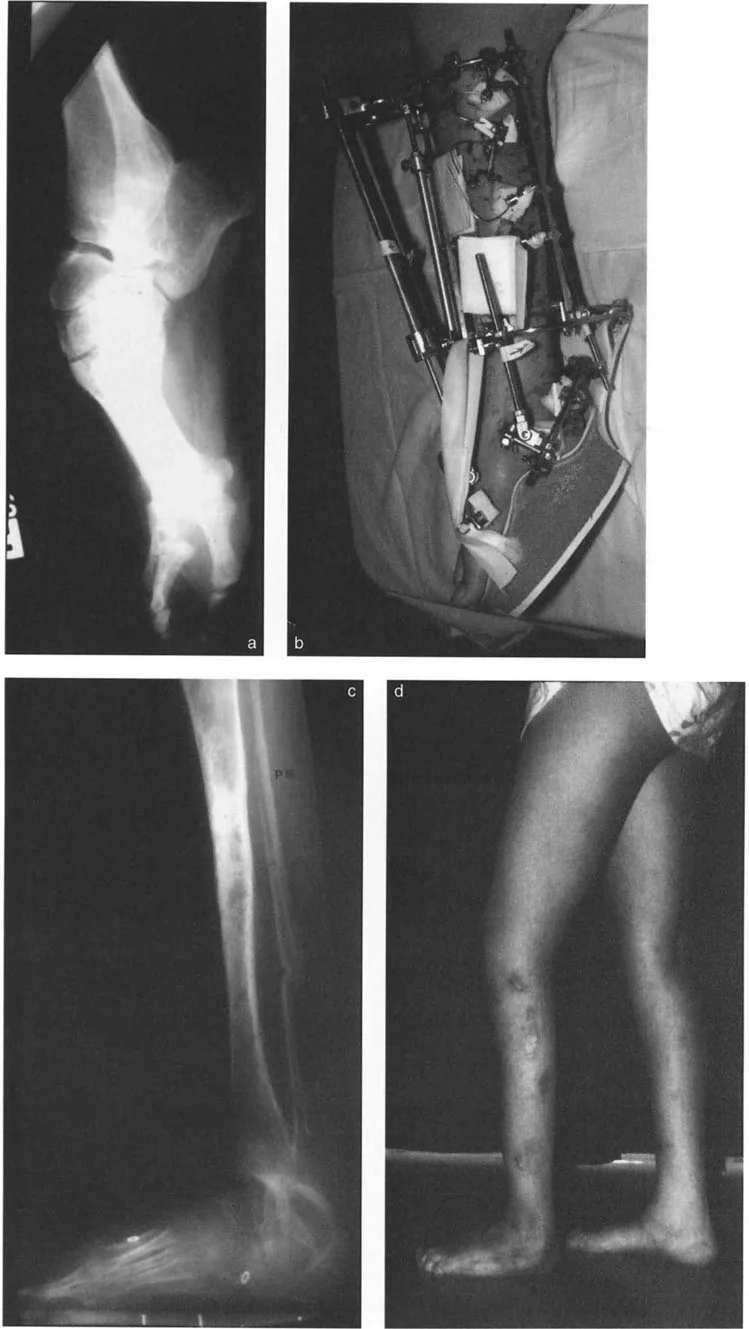

أنواع جراحات قطع العظم فوق الكاحل (Supramalleolar Osteotomy)

جراحة قطع العظم فوق الكاحل (SMO) هي الإجراء الأكثر شيوعًا لتصحيح تشوهات قصبة الساق البعيدة. تتضمن هذه الجراحة قطعًا دقيقًا في عظم الساق (القصبة) فوق مفصل الكاحل مباشرة، ثم إعادة محاذاة العظم وتثبيته في الوضع الصحيح. هناك عدة أنواع من هذه الجراحة:

1. قطع العظم الإسفيني الفاتح (Opening Wedge Osteotomy):

• يتم عمل قطع في العظم ثم فتح فجوة صغيرة فيه. تُملأ هذه الفجوة عادةً بترقيع عظمي (من جسم المريض أو من متبرع).

• المميزات: يحافظ على طول الطرف، وهو مفيد إذا كان المريض يعاني أيضًا من اختلاف في طول الساقين.

• العيوب: يتطلب ترقيعًا عظميًا، ويستغرق وقتًا أطول للالتئام، وقد يزيد من توتر الأنسجة الرخوة حول العظم.

2. قطع العظم الإسفيني المغلق (Closing Wedge Osteotomy):

• يتم إزالة قطعة صغيرة من العظم على شكل إسفين، ثم يتم تقريب أطراف العظم وربطها معًا.

• المميزات: يوفر استقرارًا عاليًا، ويسمح بالاتصال المباشر بين العظام، مما يسرع الالتئام ويسمح غالبًا بتحميل الوزن مبكرًا.

• العيوب: يؤدي إلى تقصير طفيف في الطرف، وهو ما قد لا يكون مرغوبًا في بعض الحالات.

3. قطع العظم القوسي البؤري (Focal Dome Osteotomy):

• يتم عمل قطع منحني في العظم، مما يسمح بتصحيح